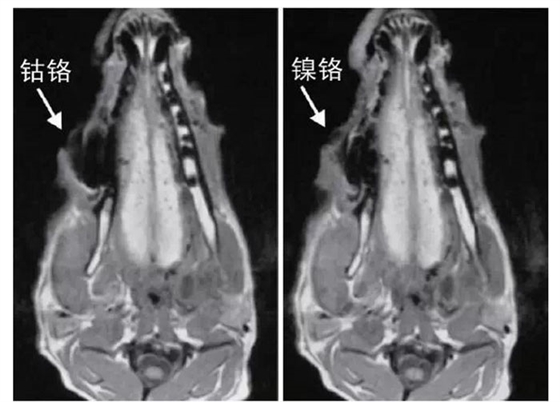

文獻研究中常使用的金屬包括鎳鉻合金、鈷鉻合金、低鈦合金、純鈦、金合金、金鈀合金、銀鈀合金等成分如表所示。大量研究得出近乎一致性的結(jié)論。金合金、金鈀合金、銀鈀合金對MRI影響甚微,與全瓷材料、丙烯酸樹脂極為相似,表現(xiàn)為修復(fù)體影像邊緣光滑、無變形、無偽影;純鈦金屬對MRI影響較小,接近于全瓷材料;但有的研究卻發(fā)現(xiàn)純鈦在核磁共振場中也產(chǎn)生偽影,但偽影涉及的掃描層數(shù)較少;低鈦合金(鈦合金)對MRI影響較大,介于純鈦和鎳鉻合金之間,中度偽影;鎳鉻合金、鈷鉻合金對MRI影響很大,鈷鉻合金更甚;表現(xiàn)為重度偽影、圖像扭曲變形(圖1、圖2)。不難看出,對MRI影響,全瓷材料、樹脂材料<金合金等貴金屬<純鈦<低鈦合金<鎳鉻合金<鈷鉻合金。有研究發(fā)現(xiàn)鈷鉻合金橋偽影大小與修復(fù)體長軸一致,影響范圍為固定橋近遠中徑2倍,頰舌徑的4倍;相同外形金屬修復(fù)體厚度增加,偽影增加。單個金屬樁核偽影可波及到上頜竇、牙槽骨、舌體、舌下腺等組織器官,但對眼底、眼內(nèi)容物、腦組織和頸椎成像基本無影響。

圖2 4種金屬冠在犬MRI檢查中的影響,圖片引自《實用口腔醫(yī)學(xué)雜志》2014第30期《4種金屬冠對磁共振成像影響的對比研究》一文,作者高嵐等